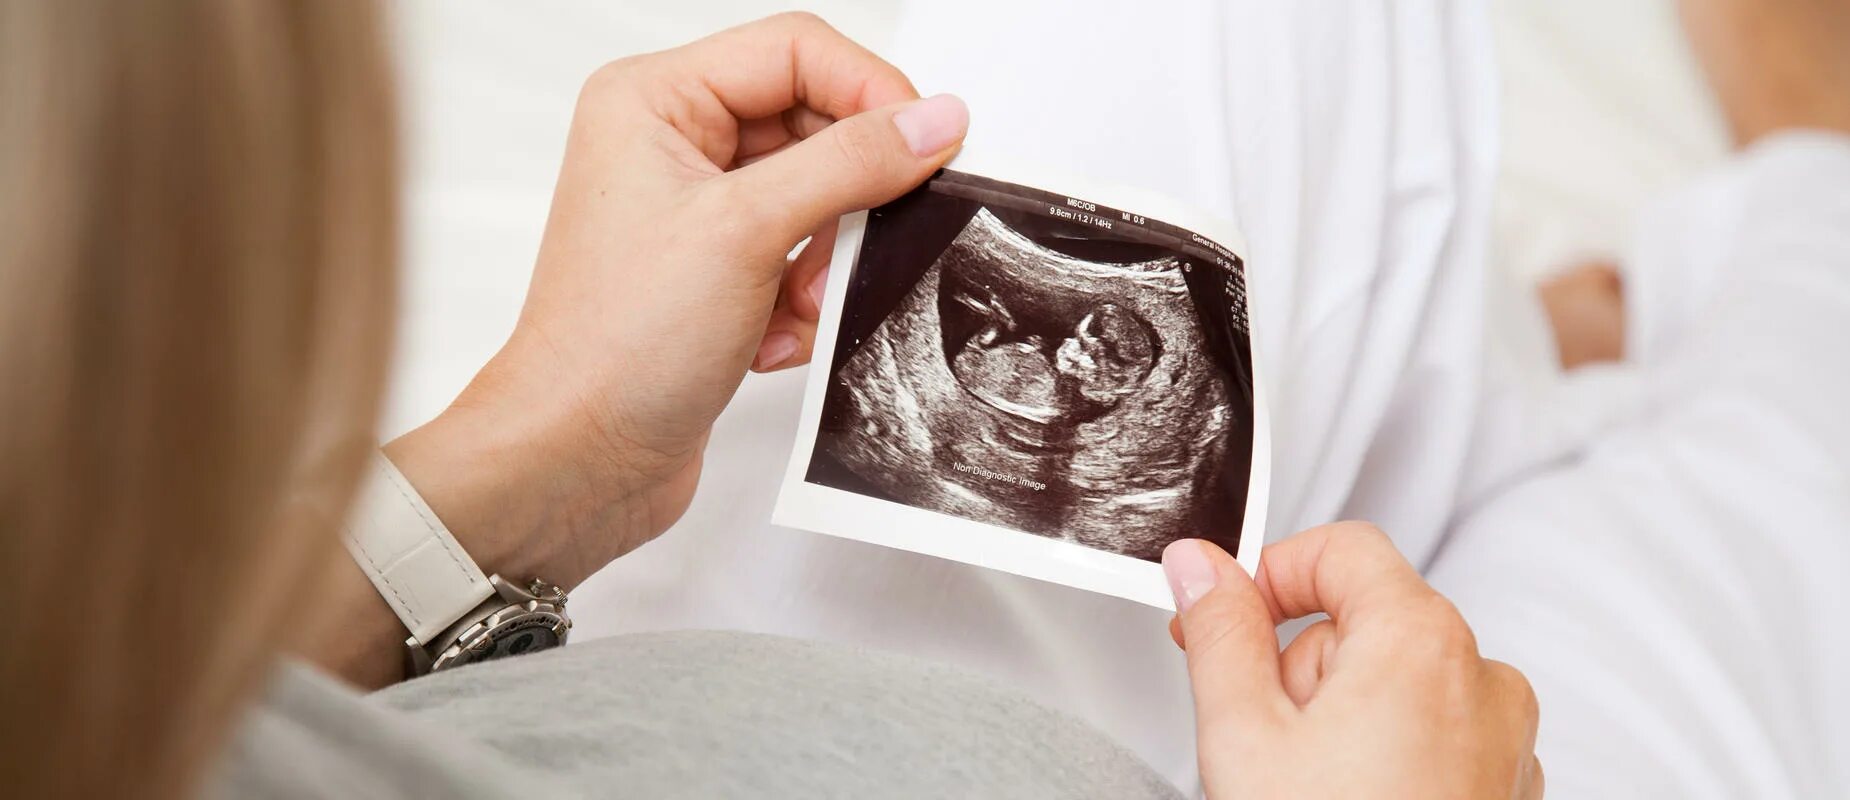

20 недель часто шевелится